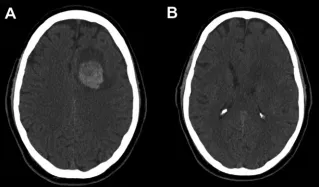

增强CT扫描揭示出险情:其左侧额上回区域发现一个与硬脑膜相连的类圆形病灶,内部已见出血迹象(图1A,B)。诊断指向一种罕见的脑膜瘤相关出血。

就在入住地区医院约6小时后,患者被紧急转往上级神经外科中心。转运途中,惊险一幕发生——患者突然陷入昏迷!经紧急抢救,生命体征方趋稳定。抵达后紧急复查CT,结果令人震惊:原病灶周围爆发大量脑实质内及脑室内出血(图1C–F),颅内情况急剧恶化。综合研判,这是一例极其罕见的、与良性脑膜瘤相关的“两阶段”复发性大出血事件,第二波出血来势汹汹,直接危及生命。